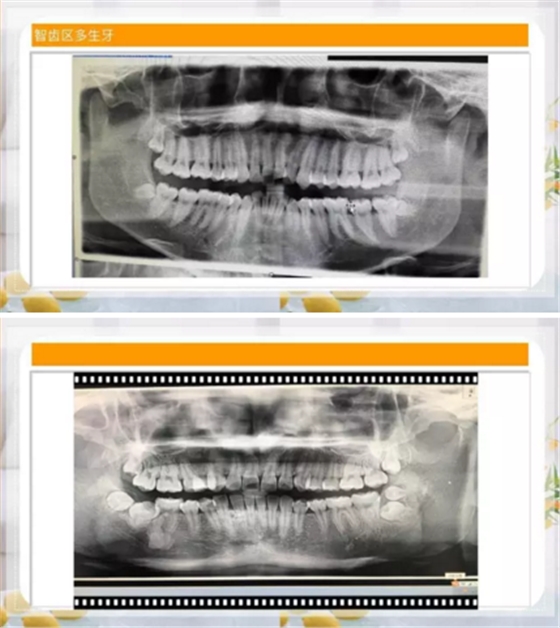

智齒區(qū)多生牙

如此親密!

如何才能完整而且沒(méi)有骨損傷的拔掉這顆牙齒呢?

那就兩個(gè)一起拔!

其實(shí)是這樣的!